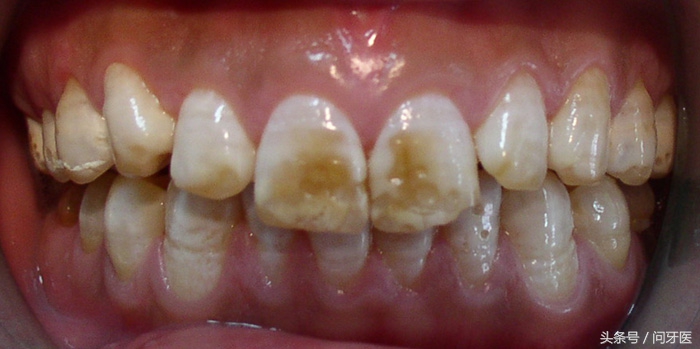

上图这种类型叫氟斑牙,也叫斑釉,是由于长期饮用含氟水。早期我国一些地方自来水放氟量偏高,长期饮用这种自来水,就是导致氟斑牙的根本原因。基本上我们能接触到的氟斑牙患者都在30岁左右了,95后很少见到。现在往自来水大量加氟的比较少见了。

这类氟斑牙,没有特别好的治疗办法,轻度的可以做冷光美白,能使牙齿整体白三个色阶,冷光美白并不能治愈氟斑牙,斑块还是有的,只是模糊白了。

中度重度的患者,可以考虑做超薄牙齿贴面。就是把牙齿档在里面,跟遮羞布一样。也能使面貌改变。但是这种技术费用三四万左右。一般需要贴面12-20颗左右。不是普通人能享受的。